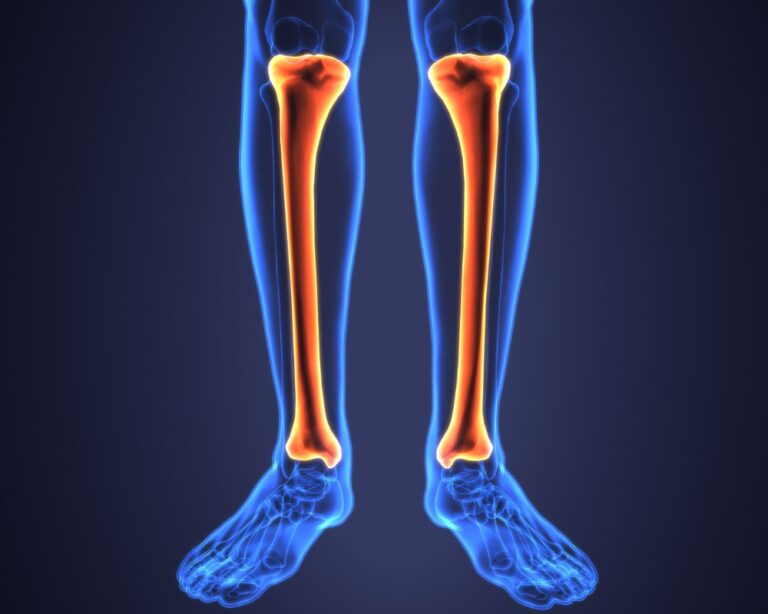

Flexor Carpi Radialis Diagram